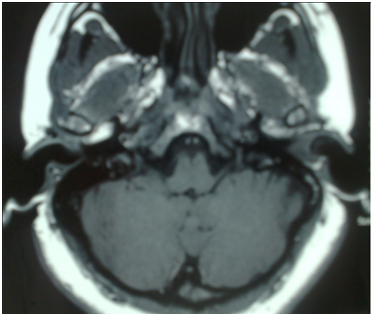

CT scan temporal bone shows left mastoid cells occupied by soft tissue density suggestive of chronic disease and EAC with the presence of soft tissue density, the tympanic cavity is also occupied by same soft tissue density that erodes its walls and no ossicular chain is observed. Carotid artery, jugular fossa, semicircular canals, cochlea and other structures unchanged (Figure 2). The right ear is normal. The skull MRI shows a hypointense occupying the left EAC on T1 that becomes hyper intense in T2 sequence and shows a heterogeneous enhancement when contrast is applied (Figure 3).

Figure 3 T1 sequence MRI Scan with a hypointense lesion in the left EAC and tympanic cavity.